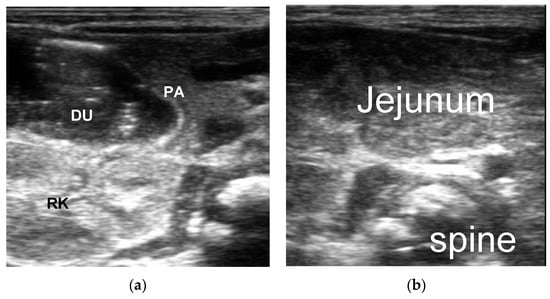

3.2. The Ultrasonic Manifestations

3.2.1. The Ultrasonic Signs of Intestinal Obstruction

3.2.2. The Corresponding Ultrasound Findings of Diseases Leading to Neonatal Ileus